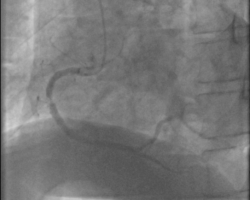

- Coronarographie : sténose coronaire droite moyenne

Patient de 67 ans consultant en urgence pour baisse d’acuité visuelle de l’œil droit de survenue brutale sans douleur ni rougeur (juillet 2018). Diagnostic d’OACR fait en ophtalmologie amenant à effectuer un bilan d’AVC. Le patient est transféré au caisson hyperbarre (protocole de recherche clinique sur les OACR) et développe une douleur thoracique lors d’une séance. Un ECG est réalisé en urgence avec diagnostic d’un SCA ST- en cours de constitution. Arrêt de la séance et transfert en cardiologie pour coronarographie qui montre une resténose significative de la coronaire droite moyenne au niveau d’un ancien stent coronaire posé en 2015. Il a bénéficié d’une angioplastie avec implantation d’un stent actif. Les suites de procédure sont simples et sans complication.

- Coronarographie : resténose significative intra stent de la droite moyenne.